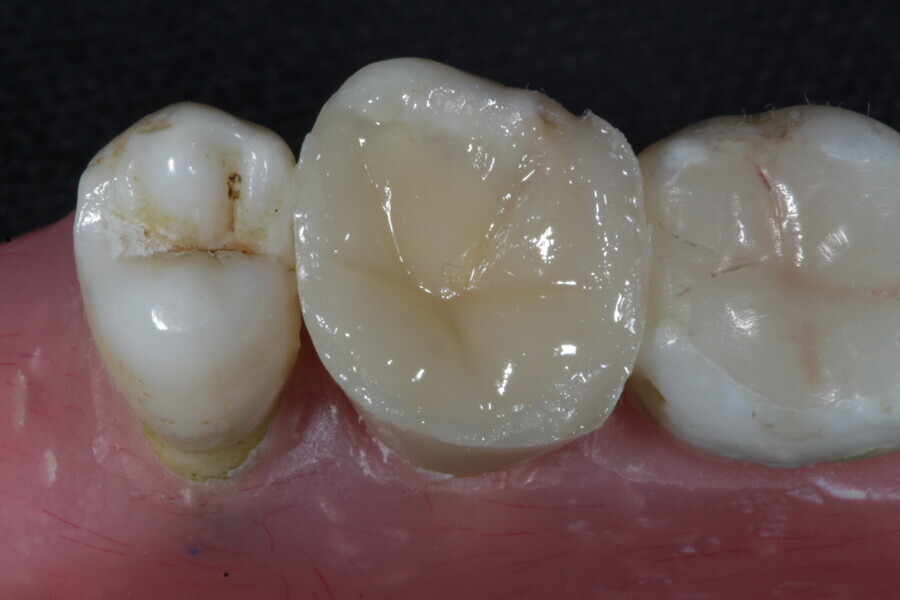

1. direct restoration using a fibre-reinforced flowable composite and membrane cube after endodontic treatment (Figs. 21–35); and

The second step focuses on reinforcing the restoration through careful fibre and FRC selection and placement. Tooth preparation should involve minimal removal of tooth structure to preserve as much natural tooth as possible in preparing the cavity for the restoration. Fibres or layers of FRC (flowable, paste, cube, etc.) are then strategically placed within the prepared tooth and composite material to reinforce areas susceptible to high stress and occlusal forces based on occlusal contact mapping. This strategic selection and placement of fibres and layers of FRC is crucial for enhancing the strength and longevity of the restoration.

The third step is to restore the tooth to its natural form, function and aesthetics. Composite resin, along with fibres or fibre-reinforced flowable or fibre-reinforced dentine substitute materials, is carefully applied to the prepared tooth structure. A layering technique is often used to ensure proper adhesion and integration of the reinforced materials with the composite material, enhancing the overall strength and functionality of the restoration. The composite resin is then polymerised using a curing light, ensuring that the materials are securely bonded within the restoration and providing a stable and long-lasting result. During this restorative process, the clinician should take special care not to expose fibres or FRC layers to the oral environment, as this can cause tissue irritation and water absorption by the materials in the long run. Therefore, the final layers of the restoration should always be a suitable aesthetic conventional composite resin.

The final step of the MiCD Fiber Filling 4R protocol is refining the restoration to ensure optimal occlusal and proximal contacts, functional comfort and aesthetics. Adjustments are made to ensure proper distribution of occlusal forces during functional occlusion, which is critical for the patient’s comfort and the functionality of the restoration. The surface of the restoration is then polished to achieve a smooth and natural appearance, enhancing the aesthetic appeal and ensuring that the restoration blends seamlessly with the surrounding teeth while reducing the possibility of plaque accumulation. This final refinement step ensures that the restoration not only functions optimally but also contributes to an aesthetically pleasing and healthy oral environment.